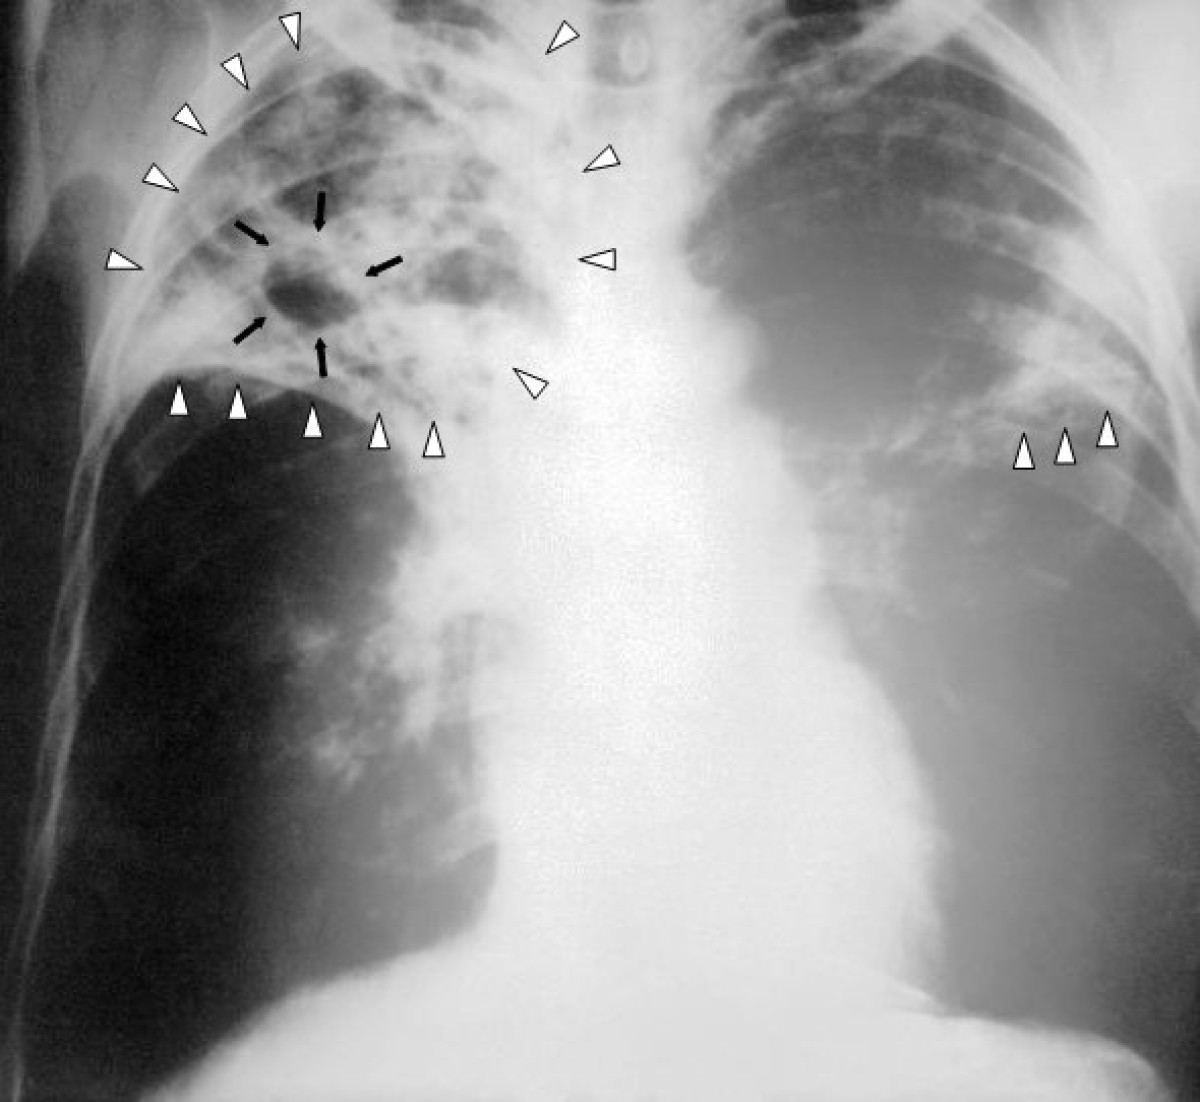

Өлкөдө жасалма интеллекттин жардамы менен кургак учук илдети аныкталууда. Бул тууралуу улуттук фтизиатрия борборунун директору Абдулаат Кадыров "Биринчи радиого" билдирди.

"Кыргызстанда Бүткүл дүйнөлүк саламаттыкты сактоо уюмунун көрсөтмөсү менен кургак учукту аныктоодо 2 жылдан бери санарип рентген аппараты жасалма интеллекттин жардамы аркылуу колдонулуп жатат.

Бүгүнкү күндө өлкөдө мындай 4 аппарат бар. Мунун жөнөкөй рентгенден айырмасы адамга тийгизген терс таасири аз",- деди ал.